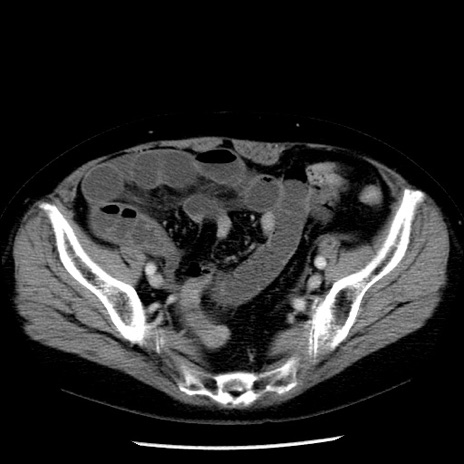

症例13(横断像)

【症例】70歳代女性

【主訴】腹痛、嘔吐

【現病歴】15時間程前(昨晩)より腹痛あり。今朝になっても症状の改善なく、嘔吐あり。腹痛も増悪あり、救急外来受診。

【既往歴】子宮癌全摘術後

【身体所見】意識清明、BP 121/72mmHg、P 74bpm、SpO2 100%(RA)、腹部:平坦・軟、腸雑音ほぼ聴取せず。下腹部・心窩部・臍左上に圧痛あり。反跳痛なし。

【データ】WBC 10600、CRP 0.15